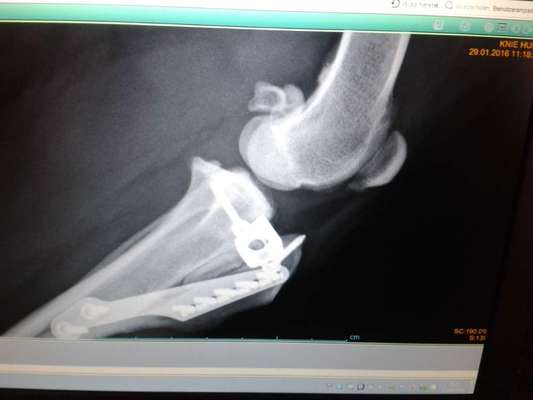

Mein mini Hund hat eine tplo gehabt vor über drei Jahren bis heute keine Probleme aber das kann nur ein richtiger Könner bei so kleinen Hunden. Das röntgen Bild ist wie aus dem Lehrbuch bei meinem Hund haben schon mehrere Fachleute gesagt